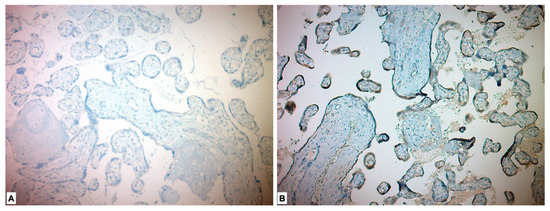

| Marker | Study Group (PE) n = 56 | Control Group n = 43 | p |

|---|---|---|---|

| CD56 n (%) | <0.001 * | ||

| High Expression | 29 (51.8) | 0 | |

| Low Expression | 27 (48.2) | 43 (100) | |

| ADAM17 n (%) | <0.001 * | ||

| High Expression | 56 (100) | 0 | |

| Low Expression | 0 | 43 (100) | |

| FGF21 | <0.001 * | ||

| High Expression | 55 (98.2) | 0 | |

| Low Expression | 1 (1.8) | 43 (100) | |